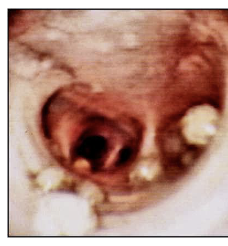

Adults in nodules in trachea of dogs

How does oslerus osleri present clinically?

Tracheo-bronchitis

Coughing

How do you diagnose oslerus osleri?

Young dogs, 1-2 years old (PPP = 10-18 weeks)

Bronchoscopy to identify nodules